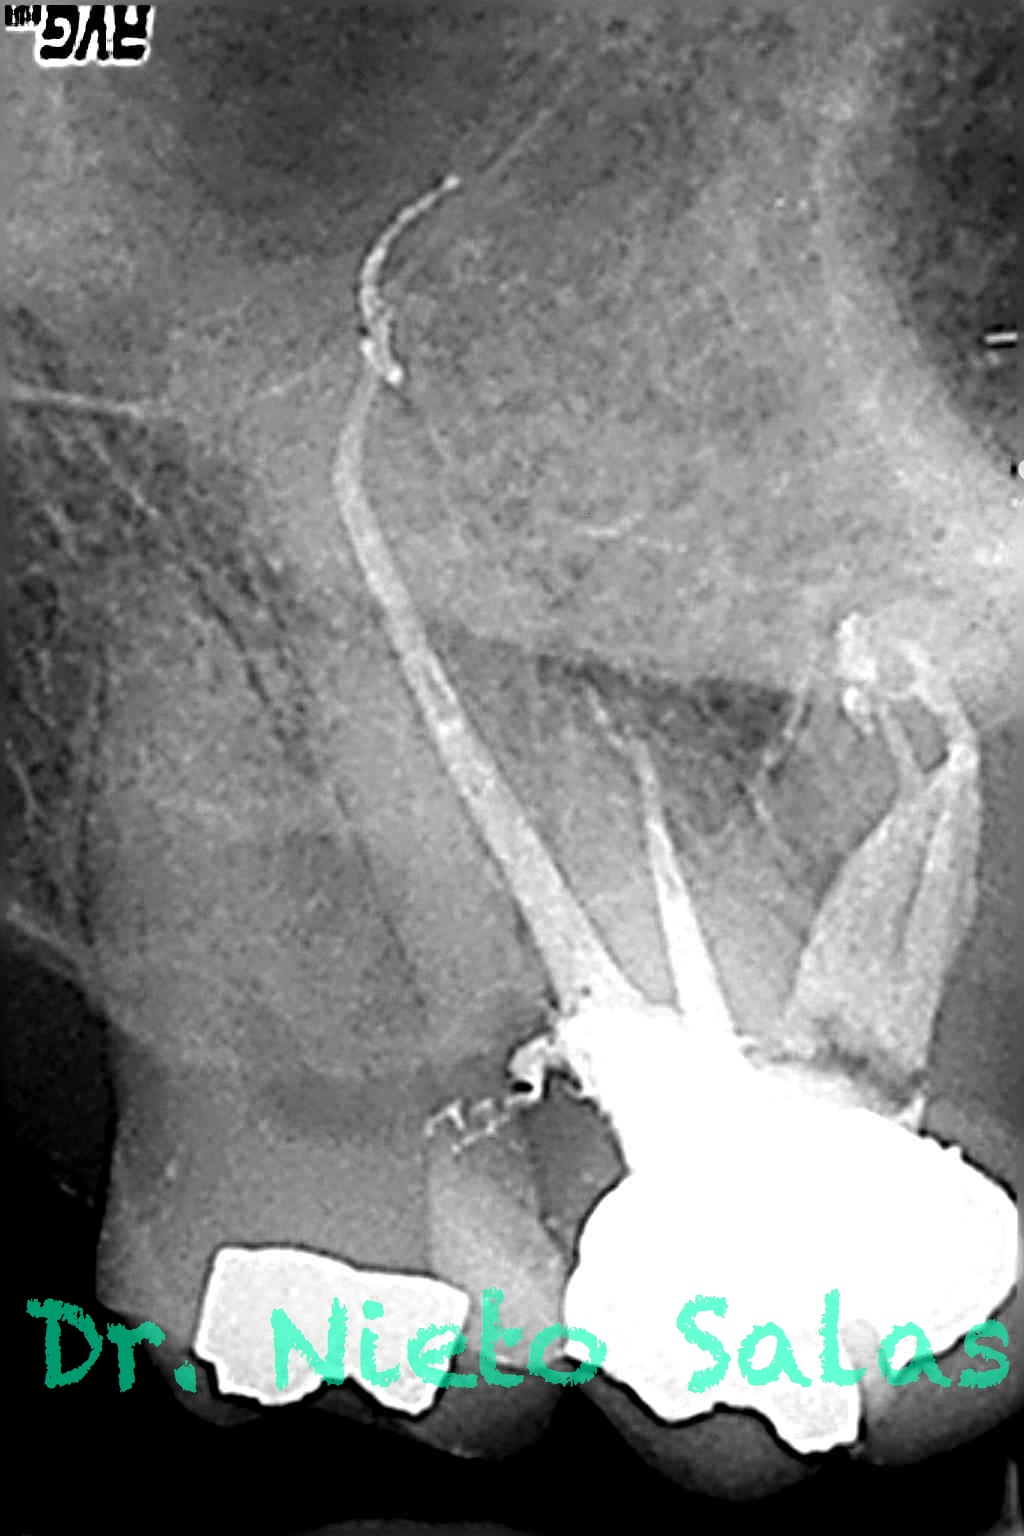

Os presento unos casos de varios molares superiores, con tres conductos mesiovestibulares con un foramen o con dos.

Una vez que tenemos medidas, obturamos los conductos: